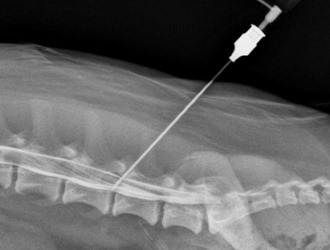

- рентгенография: на рентгеновских снимках будут видны костные наросты по краям шейных позвонков;

- миелография: этот метод используется для оценки состояния спинномозгового канала;